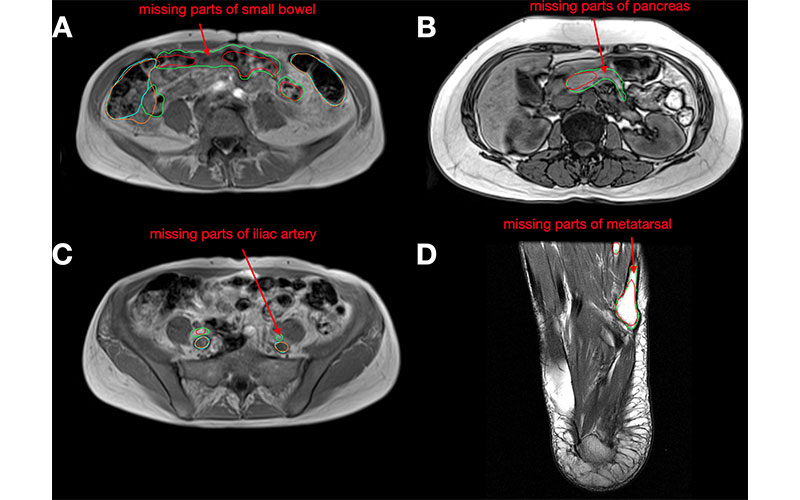

Examples of failure cases on axial MRI scans from the MRI test set. (A) The small bowel model prediction (red) is missing parts compared with the reference segmentation (green). The colon prediction (orange) overreaches the reference segmentation (cyan). (B) The pancreas model prediction (red) is missing parts compared with the reference segmentation (green). (C) The iliac artery prediction (red) is missing parts compared with the reference segmentation (green). The iliac vein prediction (orange) is very similar to the reference segmentation (cyan). (D) The metatarsal model prediction (red) is missing parts compared with the reference segmentation (green).